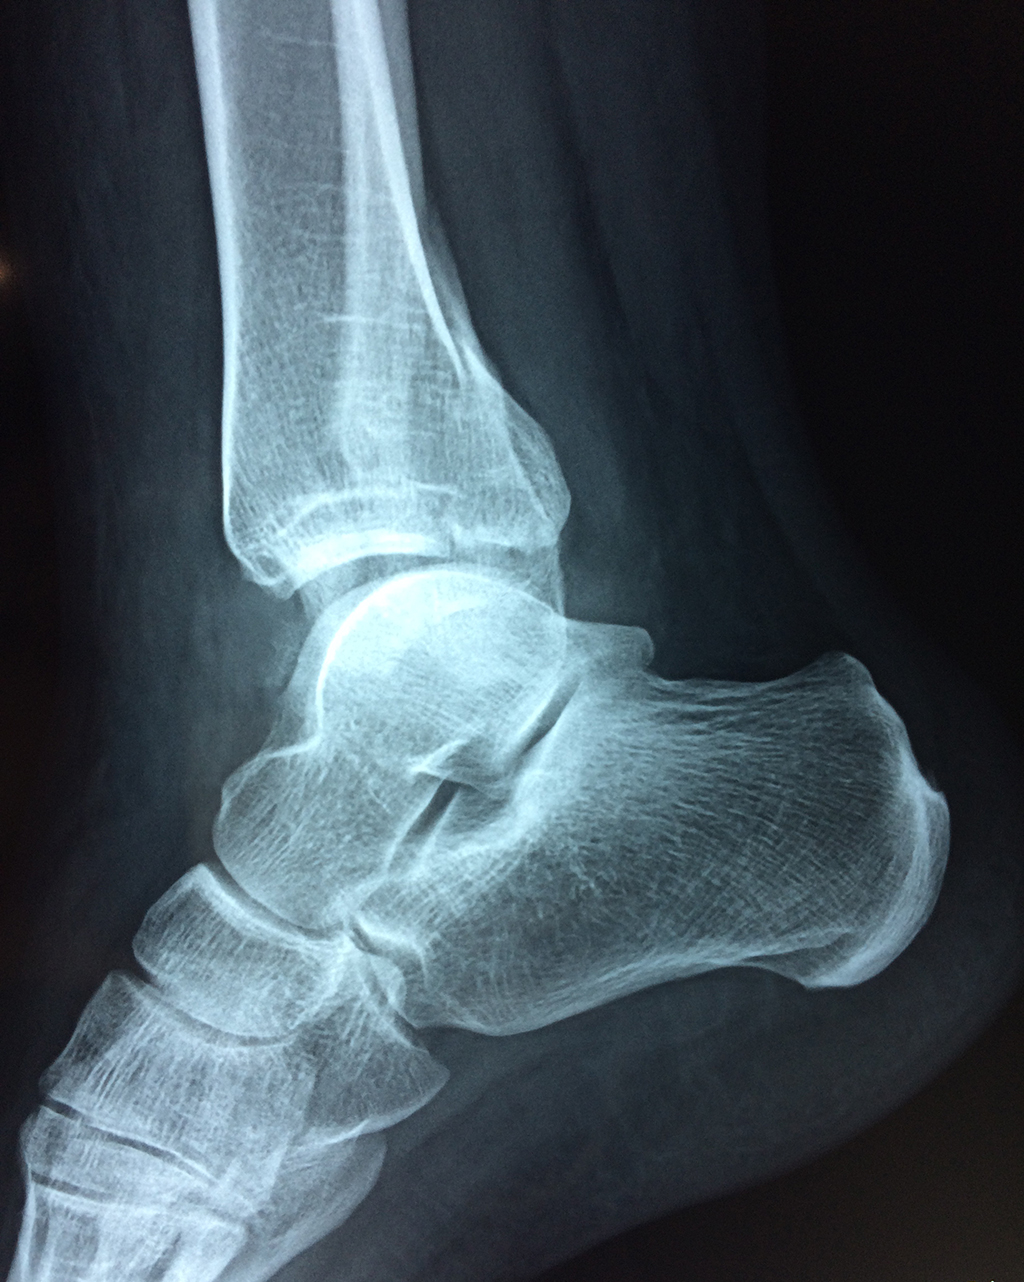

Una fractura de tobillo es la rotura de uno o más de los huesos del tobillo. Estas fracturas pueden ser:

- Producirse en uno o ambos lados del tobillo.

- La fractura se extiende hasta la articulación del tobillo (fractura intra-articular).